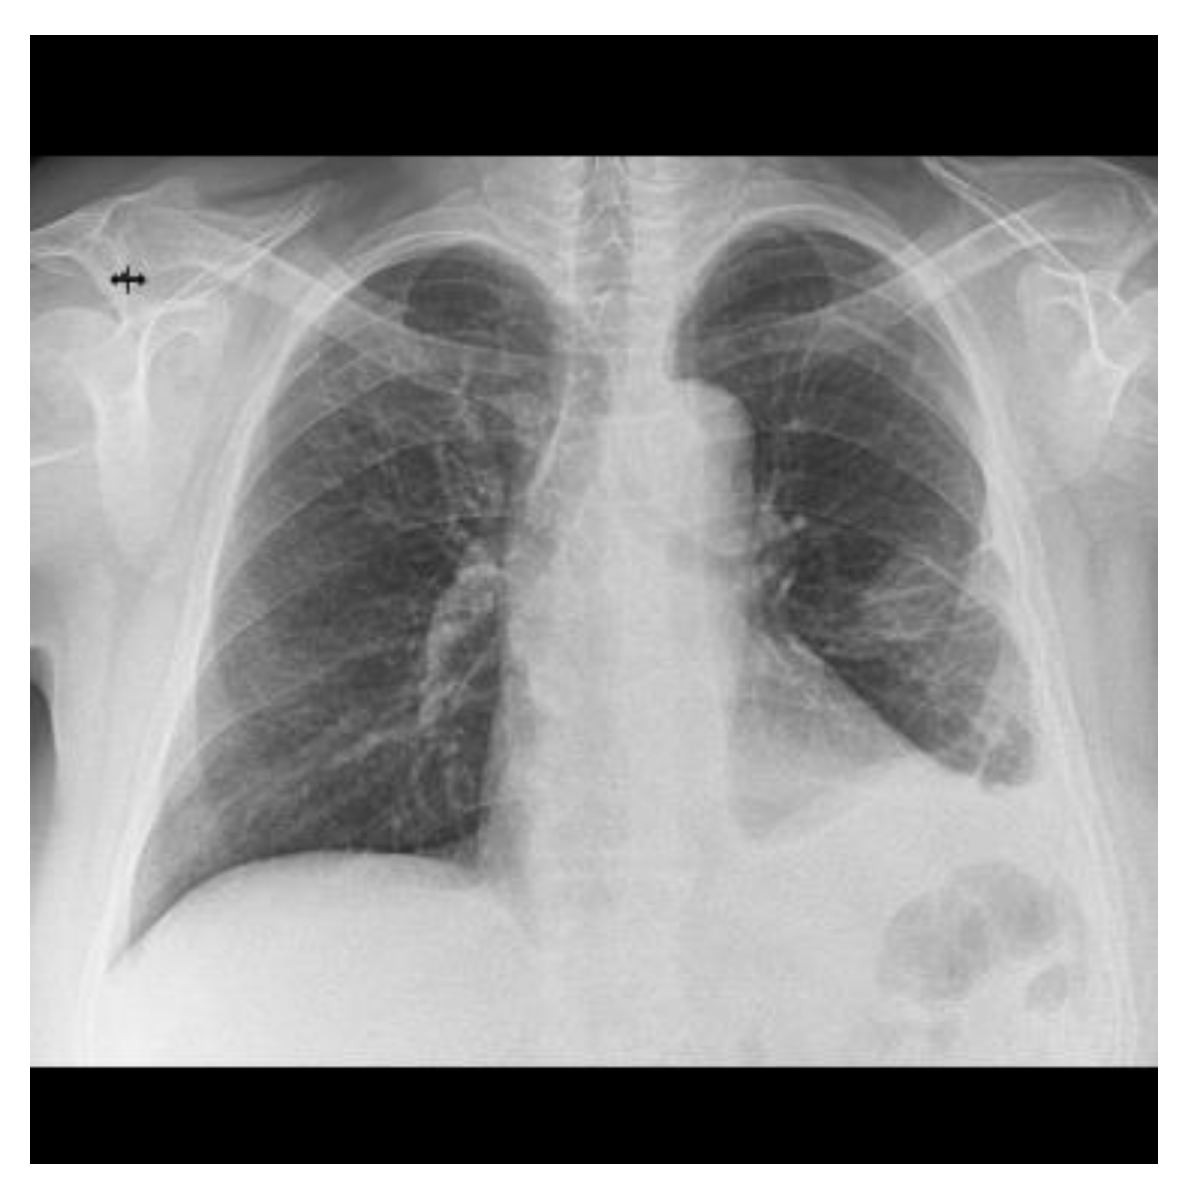

2.4. Follow-Ups